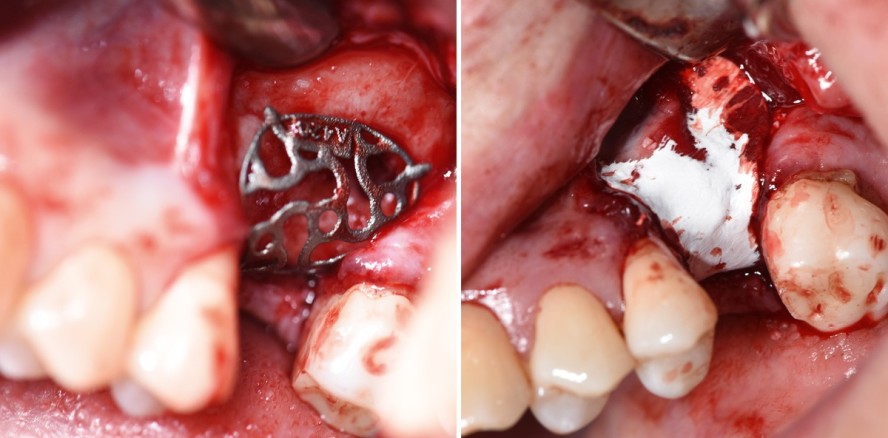

In Lokalanästhesie wird wie in unserem Fallbeispiel ein Split Flap präpariert. Erschwerend kommt bei den Patienten oft hinzu, dass sie nach einer Zahnentfernung und mehreren Voroperationen vernarbtes und schlecht durchblutetes Weichgewebe im OP-Gebiet aufweisen. Intraoral imponierten in unserem Fallbeispiel deutlich von bukkal einstrahlende Narbenzüge (Abb. 6). Generell muss das Periost scharf durchtrennt werden, um später eine spannungsfreie Deckung und einen dichten Nahtverschluss zu ermöglichen. Der Lappen sollte auch nach lingual bzw. palatinal mobilisiert werden, da der dreidimensionale Titankäfig oft den Kieferkamm umschließt. Danach folgen das Debridement von Narbengewebe und die Darstellung des knöchernen Defektes. Das sterile Titangitter wird danach mit einer Pinzette in den Defekt eingelegt, um die Passgenauigkeit und Lagestabilität zu überprüfen (Abb. 7).

Gefüllt wird das individuell hergestellte Titangitter im nächsten Schritt mit partikulärem Knochenersatzmaterial (Bio-Oss®, Geistlich) von ein bis zwei Millimeter Korngröße und autologem Knochen in einem idealen Verhältnis von 1:1. Der mit Augmentationsmaterial befüllte Korb wird danach unverzüglich in bzw. über den knöchernen Defektbereich plaziert (Abb. 8), wie unser Fallbeispiel veranschaulichen soll.